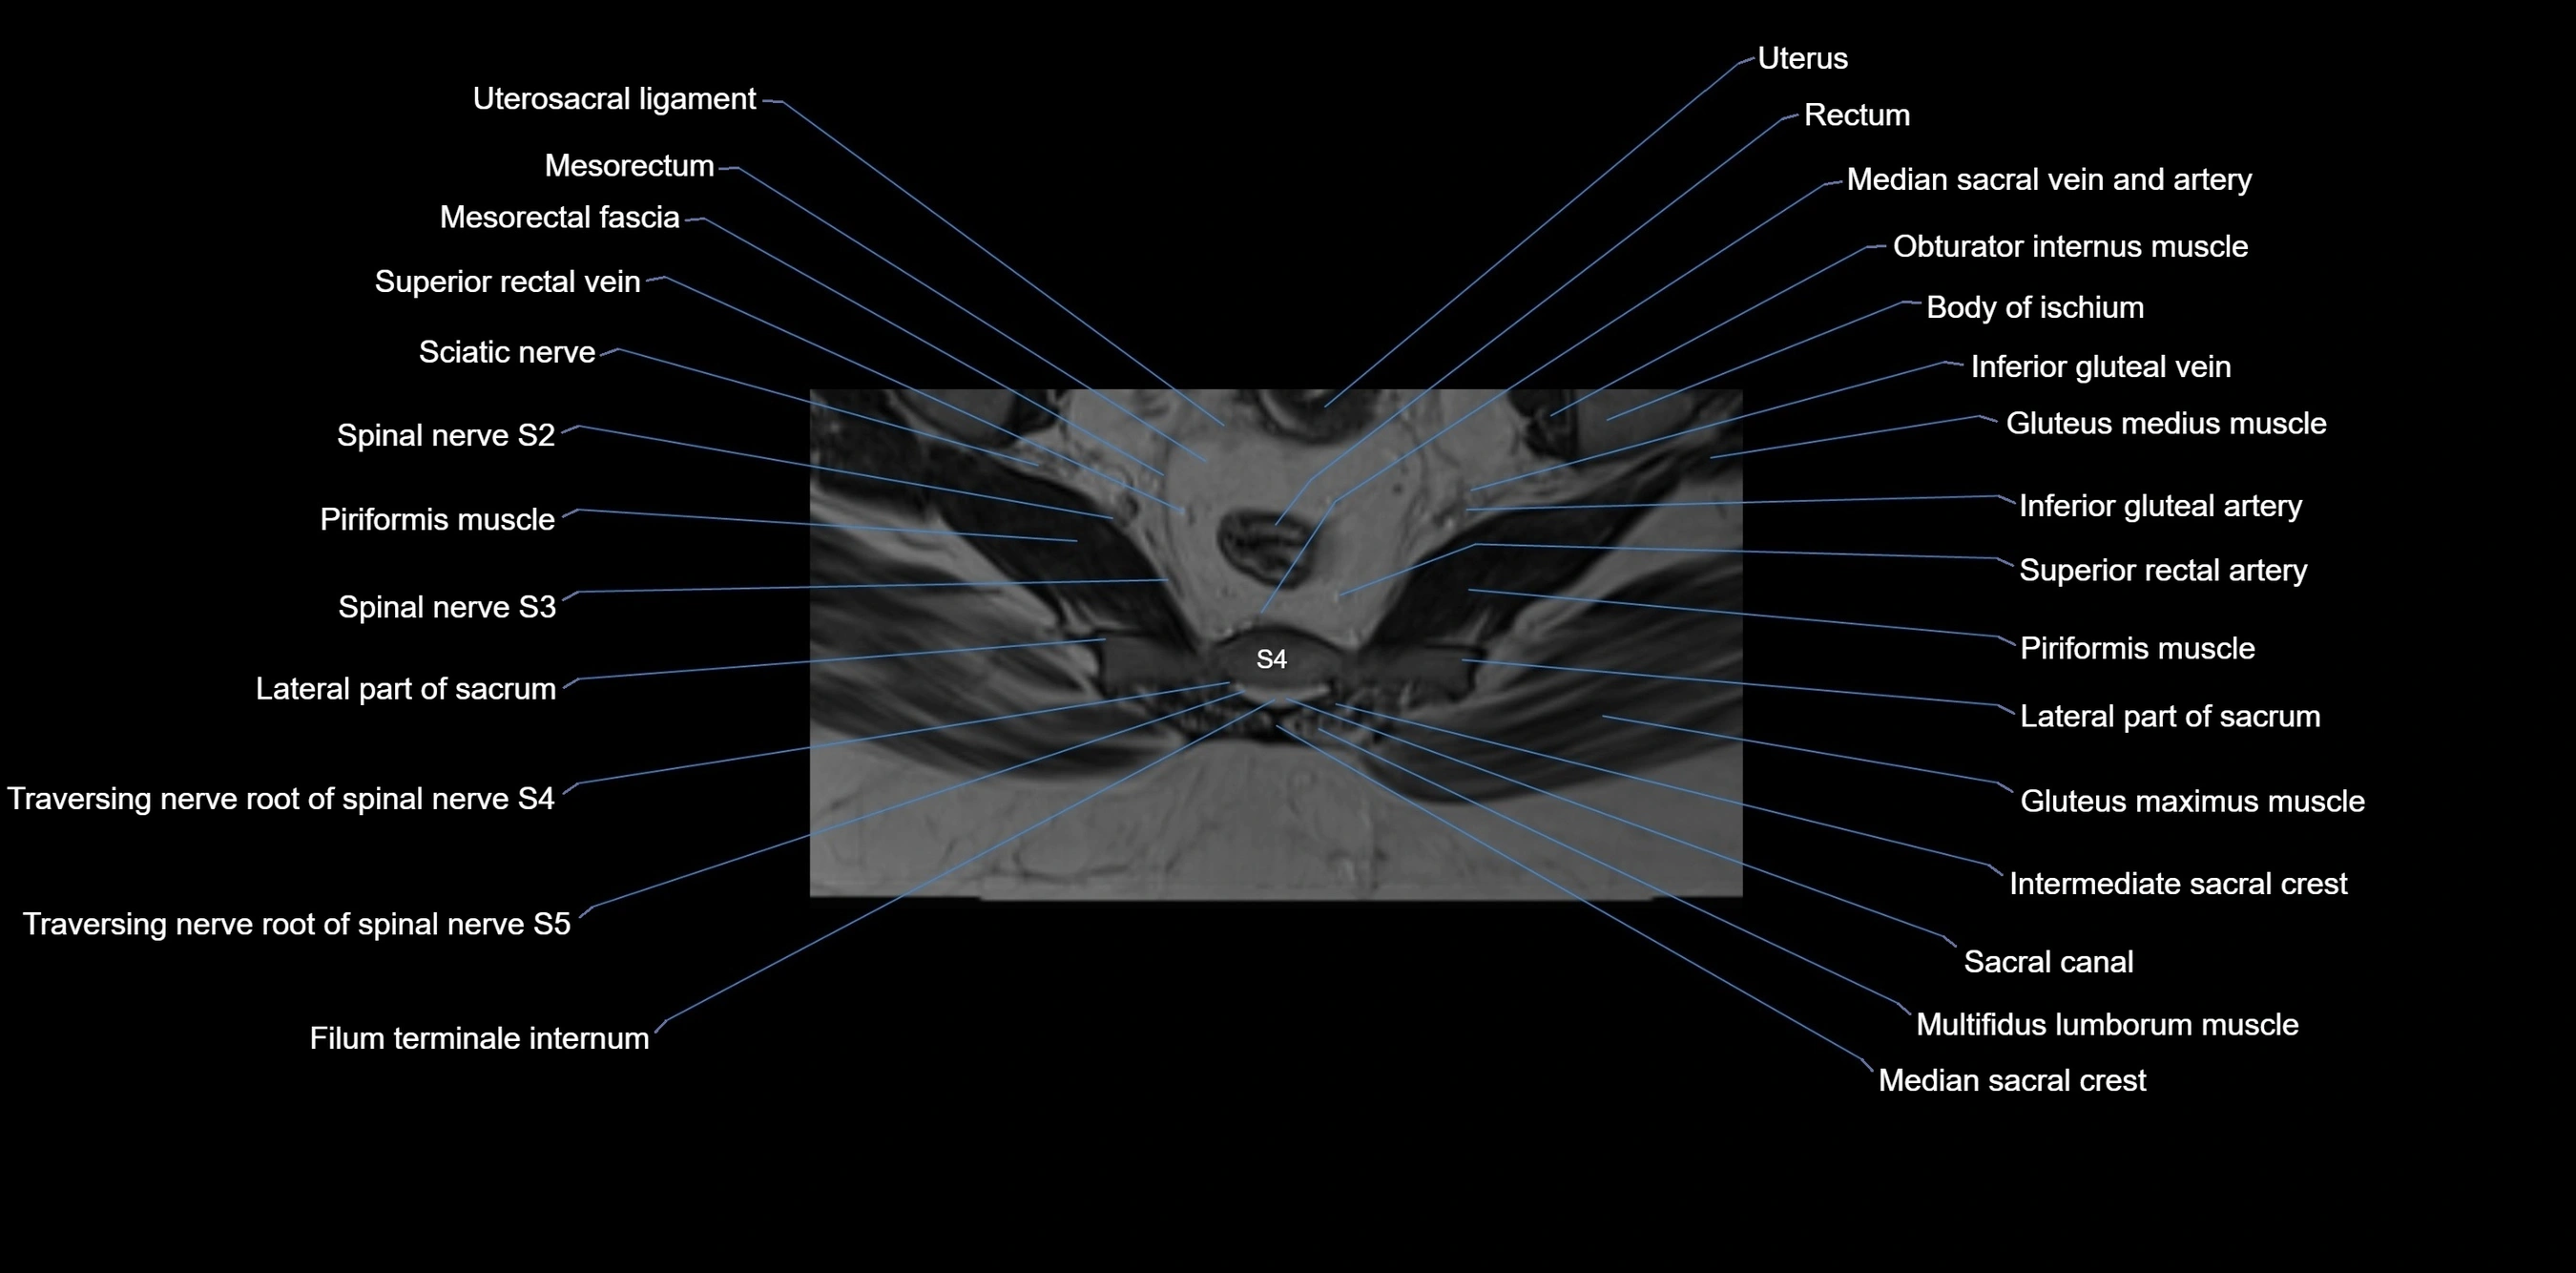

MRI Appearance

T1-weighted images:

• Cortical bone appears very low signal (dark); marrow shows intermediate signal

• Iliac fossa fat is bright against low-signal cortex

T2-weighted images:

• Cortical bone remains dark

• Marrow signal varies depending on fat content; edema or tumor shows hyperintensity

STIR:

• Suppresses fat, making bone marrow edema, fractures, or infiltrative lesions appear bright

• Excellent for trauma, sacroiliitis, and metastatic evaluation

T1 Fat-Saturated (Pre-contrast):

• Marrow: intermediate signal, fat suppressed

• Useful for detecting subtle marrow abnormalities adjacent to iliac cortex

T1 Fat-Saturated Post-Contrast (Gadolinium):

• Enhances vascularized structures, marrow pathology, tumors, and inflammatory changes

• Highlights soft tissue or bone invasion in pelvic neoplasms

MRI Non-Contrast 3D Imaging:

• Provides 3D morphology of iliac wing, crest, and articulations

• Used in preoperative planning for pelvic surgery and trauma reconstruction